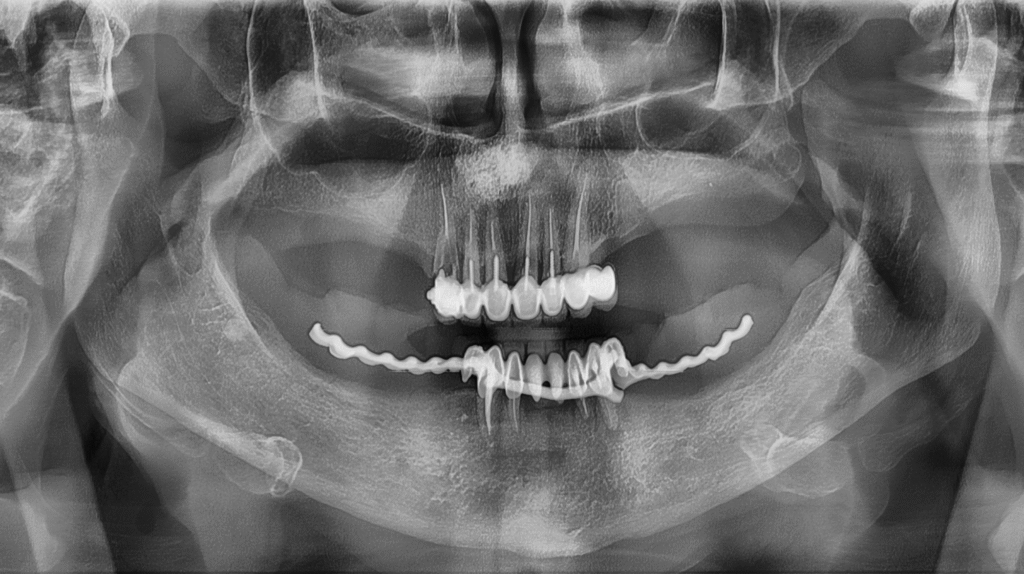

Някои образувания в лицево-челюстната зона се развиват без симптоми и се откриват едва при профилактично изследване. Кистата на назопалатиналния канал е именно такъв пример.